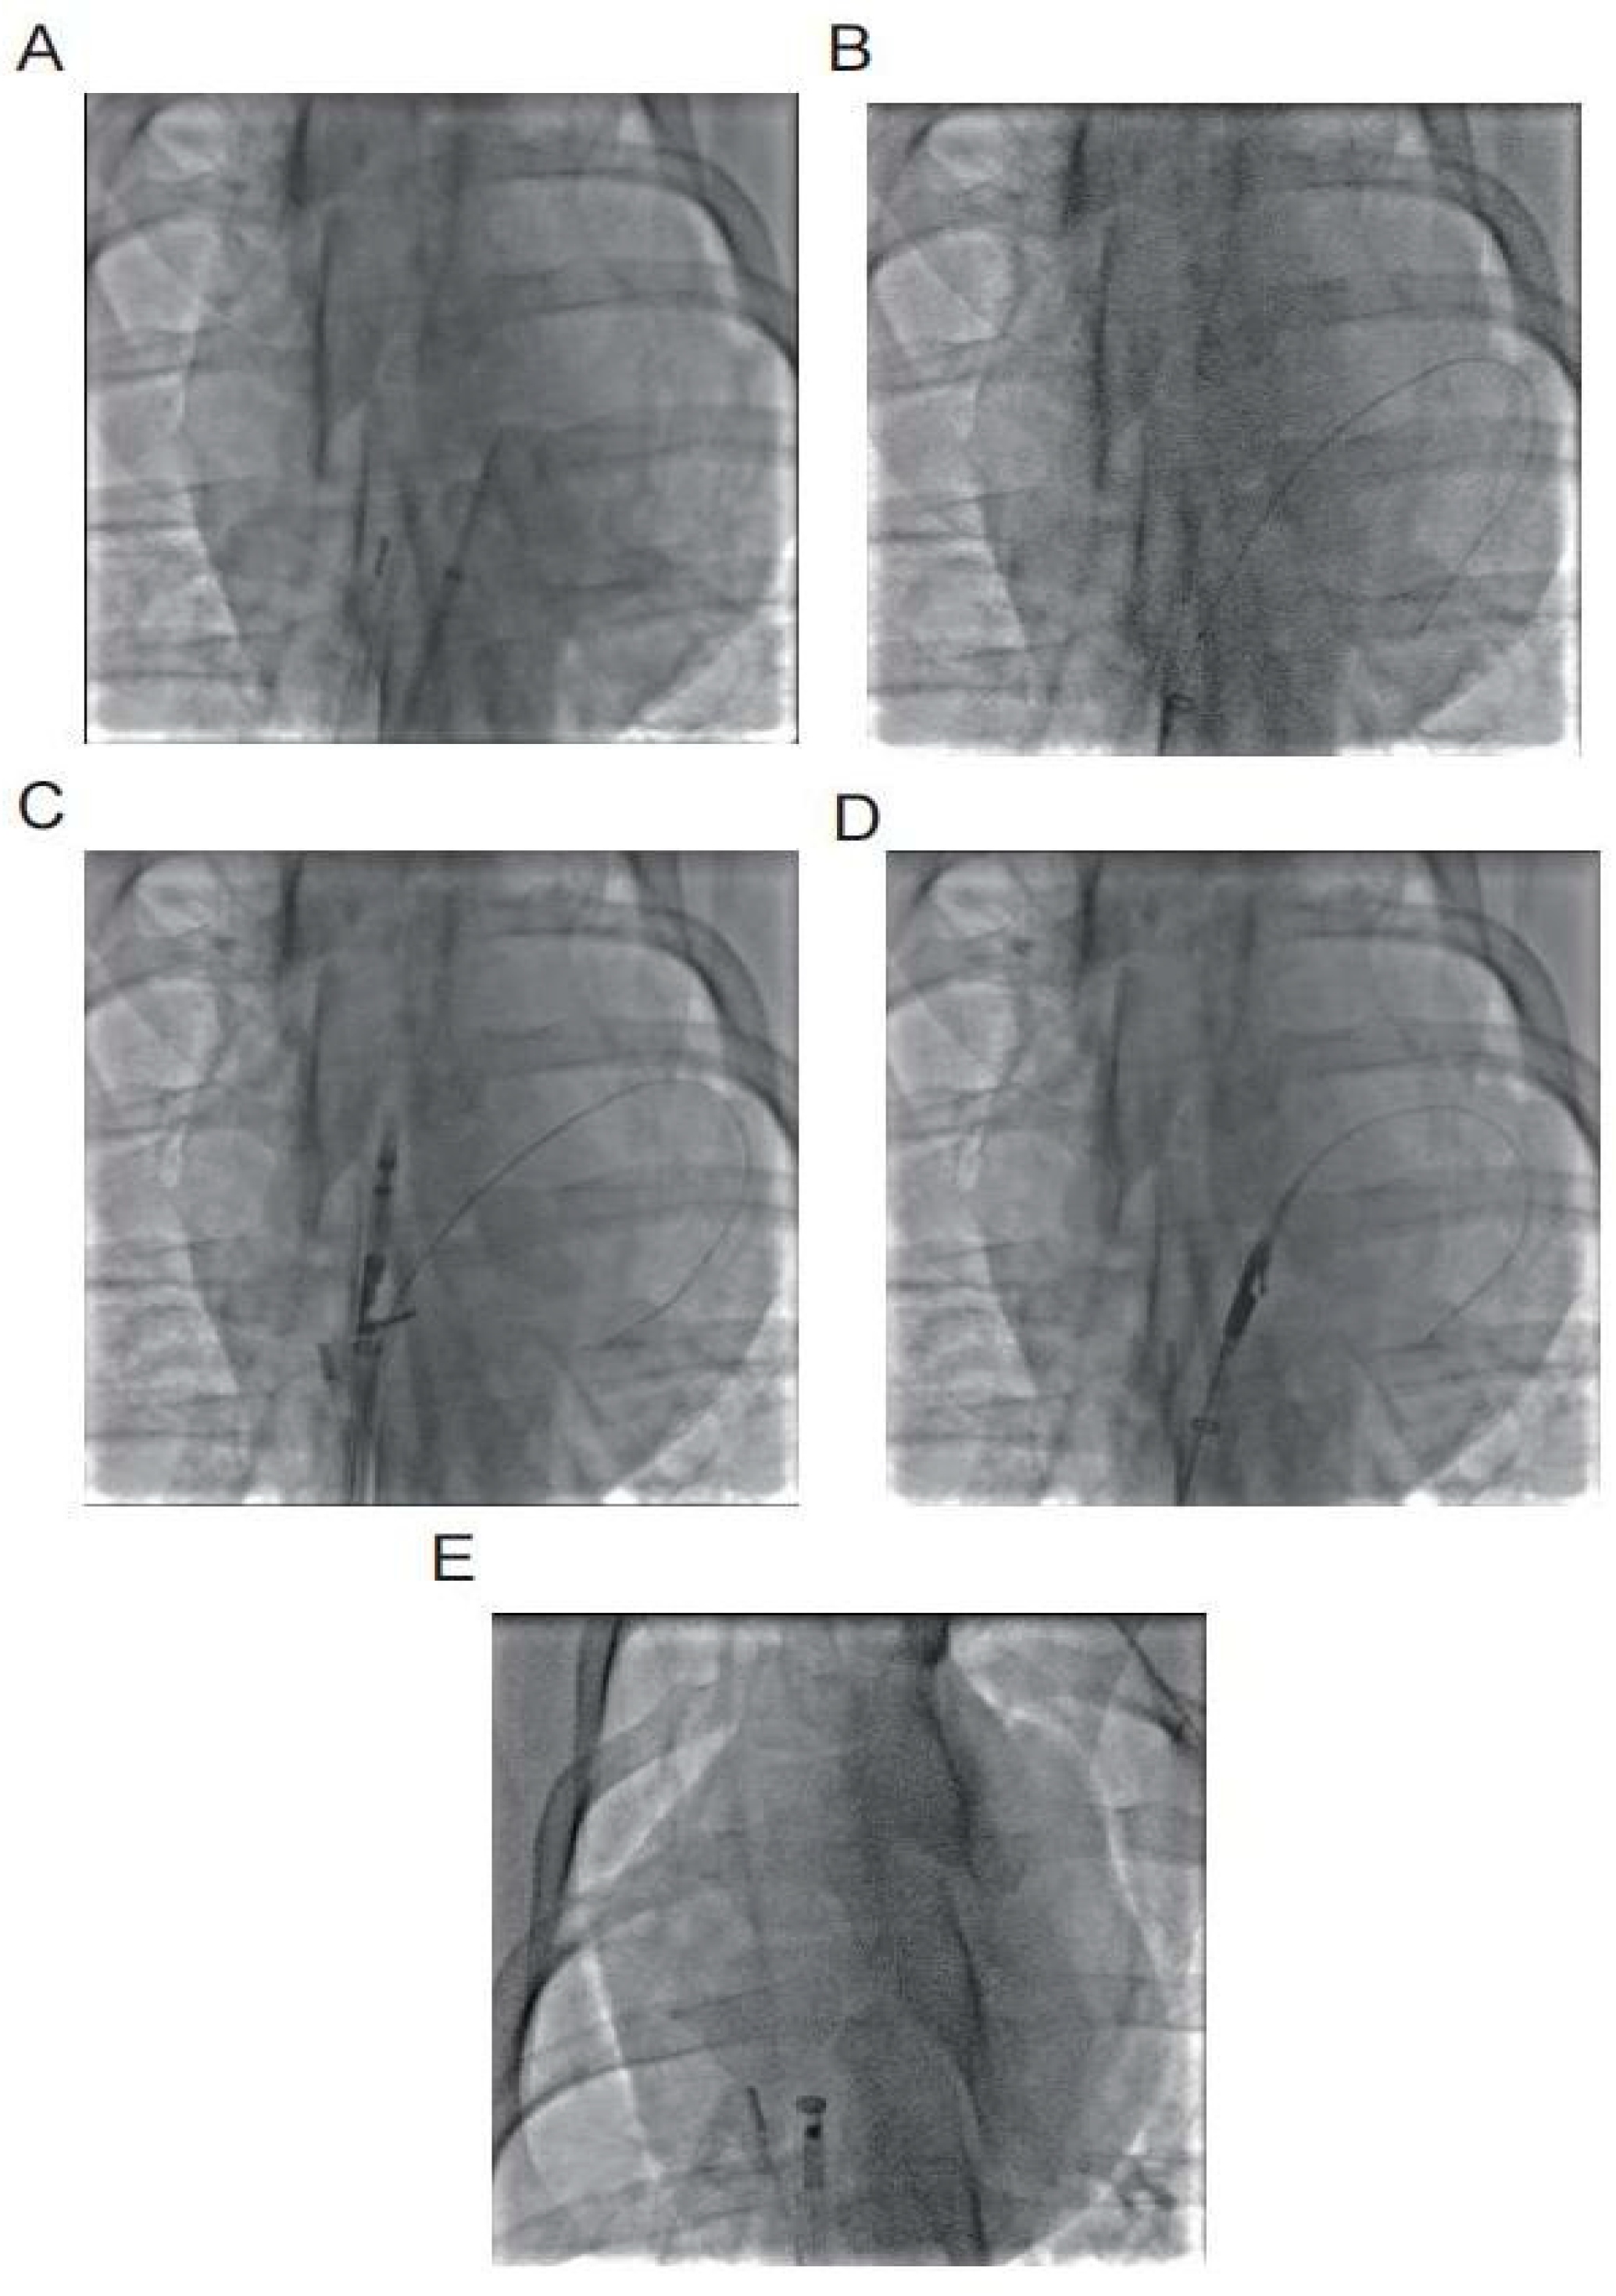

The left femoral vein was punctured to establish access for intracardiac ultrasound, while the left femoral artery was punctured for invasive blood pressure monitoring. The right femoral vein was accessed for atrial septal puncture and delivery of the PFO suture system. A guidewire was advanced from the right femoral venous sheath into the inferior vena cava and exteriorized through a 7F venous sheath. The atrial septal puncture sheath was exchanged over the guidewire, advanced through the superior vena cava into the right atrium, and the guidewire was subsequently withdrawn. An atrial septal puncture needle (tip positioned 0.5 mm inside the sheath) was advanced through the sheath, with its tail connected to a contrast-filled syringe. Under intracardiac ultrasound guidance, the needle punctured the fossa ovalis, and contrast injection confirmed entry into the left atrium (linear contrast spray), establishing the PFO model. Fig. 2A–E illustrates the stapler implantation under digital subtraction angiography (DSA) fluoroscopy.

Figure 2: (A) Atrial septal puncture into the left atrium; (B) Insert 0.035 guide wire into the left atrium; (C) Secondary septal suture opens the opening arm in the right atrium; (D) Primary septal suture opens the opening arm in the left atrium; (E) Locking device enters the right atrium.